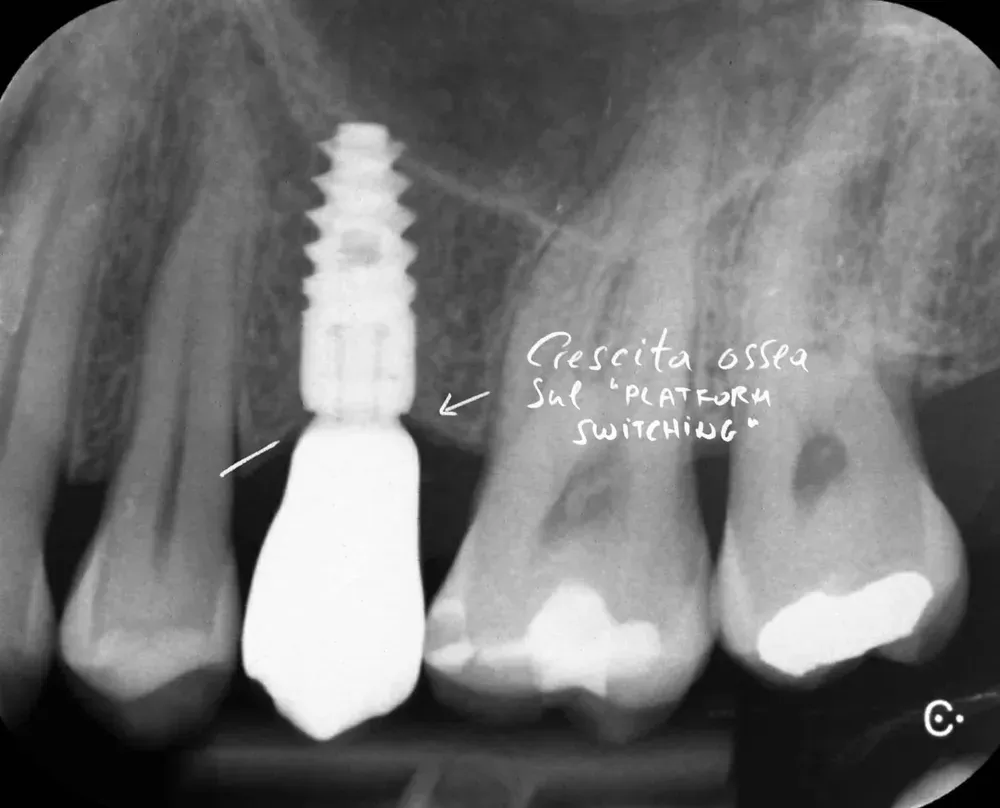

Platform switching: un’idea ottima

Il platform switching — l’uso di un abutment di diametro inferiore rispetto alla piattaforma implantare — ha basi biologiche solide. L’effetto è triplice. Il concetto è stato pubblicato da Lazzara e Porter nel 2006 (https://pubmed.ncbi.nlm.nih.gov/16515092/).

Primo: lo spostamento laterale della giunzione impianto-abutment allontana l’infiltrato infiammatorio dall’osso marginale . Secondo: le fibre collagene attorno agli abutment con platform switching si organizzano in modo circolare, stabilizzando il connettivo e proteggendo l’osso sottostante — come dimostrato istologicamente da Rodríguez e collaboratori su impianti conici nell’uomo (https://doi.org/10.11607/prd.2580) Terzo: la concentrazione dello stress meccanico si sposta dall’osso cervicale verso l’impianto stesso, anche se con un potenziale aumento dello stress sulla vite (https://doi.org/10.1111/j.1600-0501.2007.01398.x).

Sul piano clinico, Duque e colleghi hanno riportato una prevalenza di peri-implantite del 6,6% per impianti con platform switching contro il 15,6% per impianti convenzionali (https://doi.org/10.1590/1807-3107bor-2016.vol30.0005). Le revisioni sistematiche confermano una maggiore stabilità dell’osso crestale attorno agli impianti platform-switched (vedi per esempio (https://doi.org/10.1111/clr.12339).